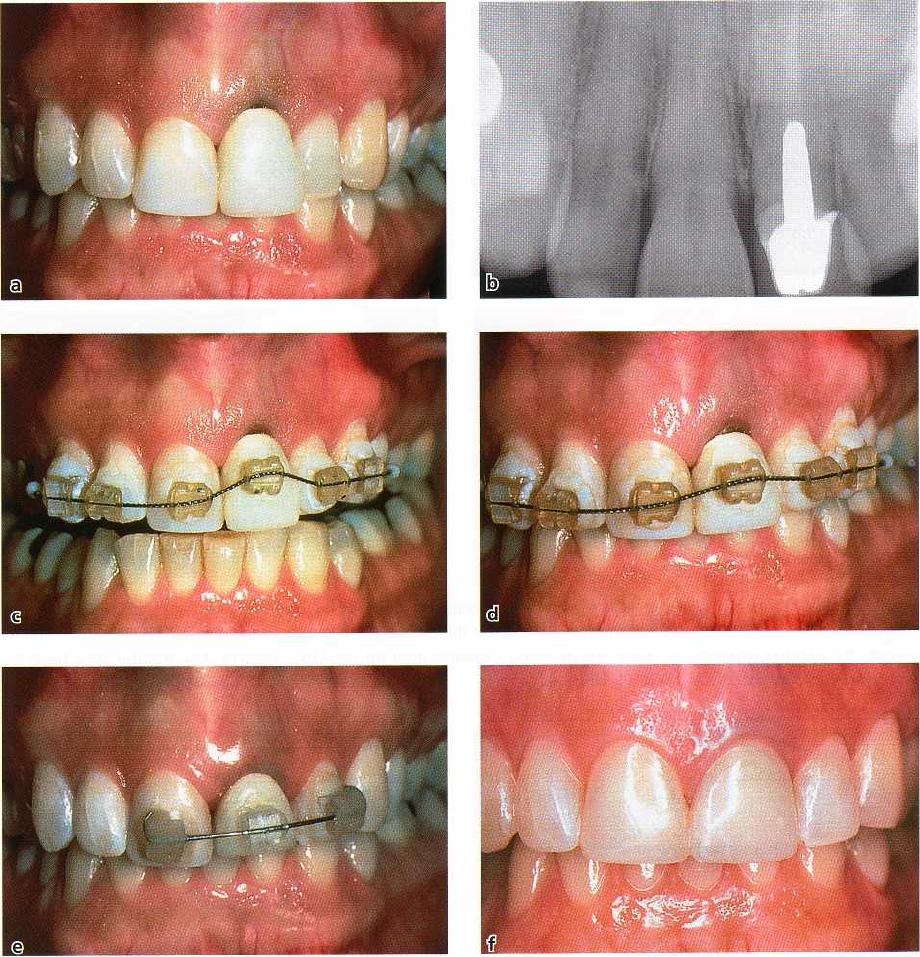

Fig.

27-76.

Sequence of steps in

the

"pouch

graft procedure"

utiliz-

ing a free graft of connective tis-

sue (CT) to expand the ridge. (A)

Cross-section of the residual eden

-

tulous ridge prior to treatment.

(

B) The horizontal incision to cre-

ate the pouch is made well to the

palatal side of the defect. The inci

sion is started partial-thickness to

leave CT to suture to when the

flap is closed. The dissection is

made supraperiosteal on the la-

bial side of the ridge to (1) ensure

an adequate blood supply within

the pedicle and

(2)

permit the flap

to expand labially or labially and

coronally free of tension. (C-D)

The CT graft can be placed as

shown for maximal buccolingual

augmentation. (E-F) If vertical

augmentation is desired, the CT

implant can be placed closer to

the crest of the ridge. As is shown

in D and F, the more the flap is

stretched or expanded to gain aug

mentation, the more difficult it is

to gain primary flap closure.